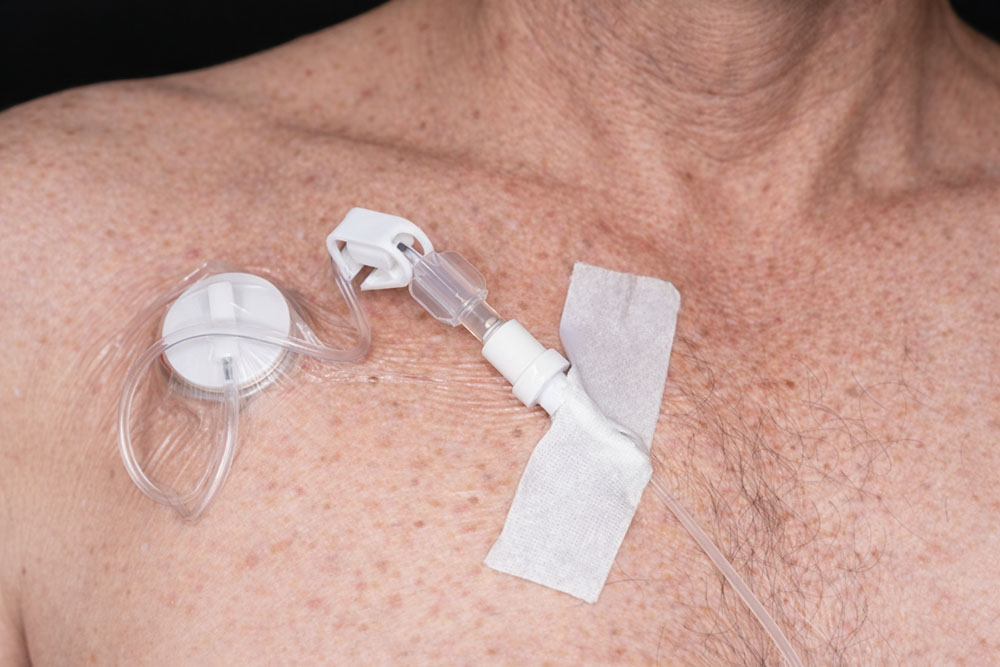

Ein Dialyseshunt, auch bekannt als arteriovenöser (AV) Shunt, ist eine lebenswichtige chirurgische Verbindung zwischen einer Arterie und einer Vene, die speziell für Patienten geschaffen wird, die eine regelmäßige Hämodialysebehandlung benötigen. Diese künstliche Verbindung wird meist im Arm angelegt und erleichtert den wiederholten Zugang zum Blutkreislauf für die Dialyse, eine Behandlung, die notwendig ist, wenn die Nieren nicht mehr in der Lage sind, das Blut effektiv zu filtern.

- Arteriovenöse Fistel (AVF): Eine direkte Verbindung zwischen einer Arterie und einer Vene, vorzugsweise im Unterarm, die einen robusten und langlebigen Zugang für die Dialyse bietet.

- Arteriovenöser Graft (AVG): Eine synthetische Röhre, die als Brücke zwischen Arterie und Vene dient, wenn die direkte Schaffung einer Fistel nicht möglich ist.